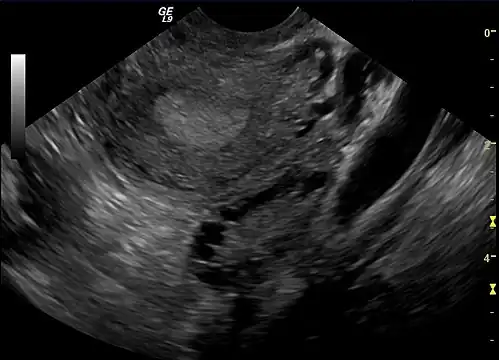

A polycystic ovary

• Polycystic ovaries: There are small cysts on one or both ovaries. Ovaries might enlarge and compress follicles surrounding the eggs. As a result, ovaries might fail to function regularly. This disease is related to the number of follicles per ovary each month, growing from the average range of 6–8 to double, triple, or more.

The syndrome acquired its most widely used name due to the common sign on ultrasound examination of multiple (poly) ovarian cysts. These "cysts" are immature ovarian follicles. The follicles have developed from primordial follicles, but this development has stopped ("arrested") at an early stage, due to the disturbed ovarian function. The follicles may be oriented along the ovarian periphery, appearing as a 'string of pearls' on ultrasound examination.[63]

Gynecologic ultrasonography first looks for small ovarian follicles.[75] To count as polycystic ovaries, at least 20 follicles need to be present, smaller than 9 mm. This used to be 12 in older diagnostic criteria.[16] A less clear marker of PCOS is enlarged ovaries.[75] Ovary need to be at least 10 cm3 to count.[16] For sexually active individuals or those that agree, a transvaginal ultrasound approach is preferred. Alternatively, AMH levels can be tested in the blood.[75] Laparoscopic examination may reveal a thickened, smooth, pearl-white outer surface of the ovary. This would usually be an incidental finding if laparoscopy were performed for some other reason, as it would not be routine to examine the ovaries in this way to confirm a diagnosis of PCOS.[78]